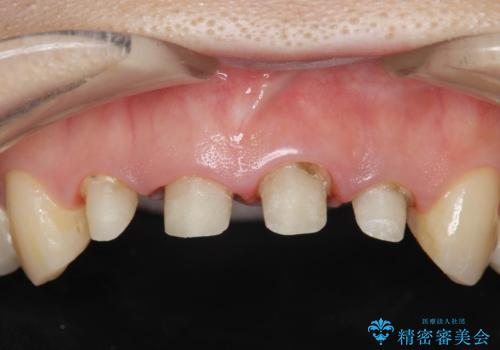

- 歯ぐきの黒っぽさ、暗い色調の前歯の改善を求めて来院されました。

金属を用いたコア・クラウンが装着されており、全ての金属を除去したのちのメタルフリー治療を計画します。

ファイバーコア・セラミッククラウンは金属を用いない審美的な治療法です。